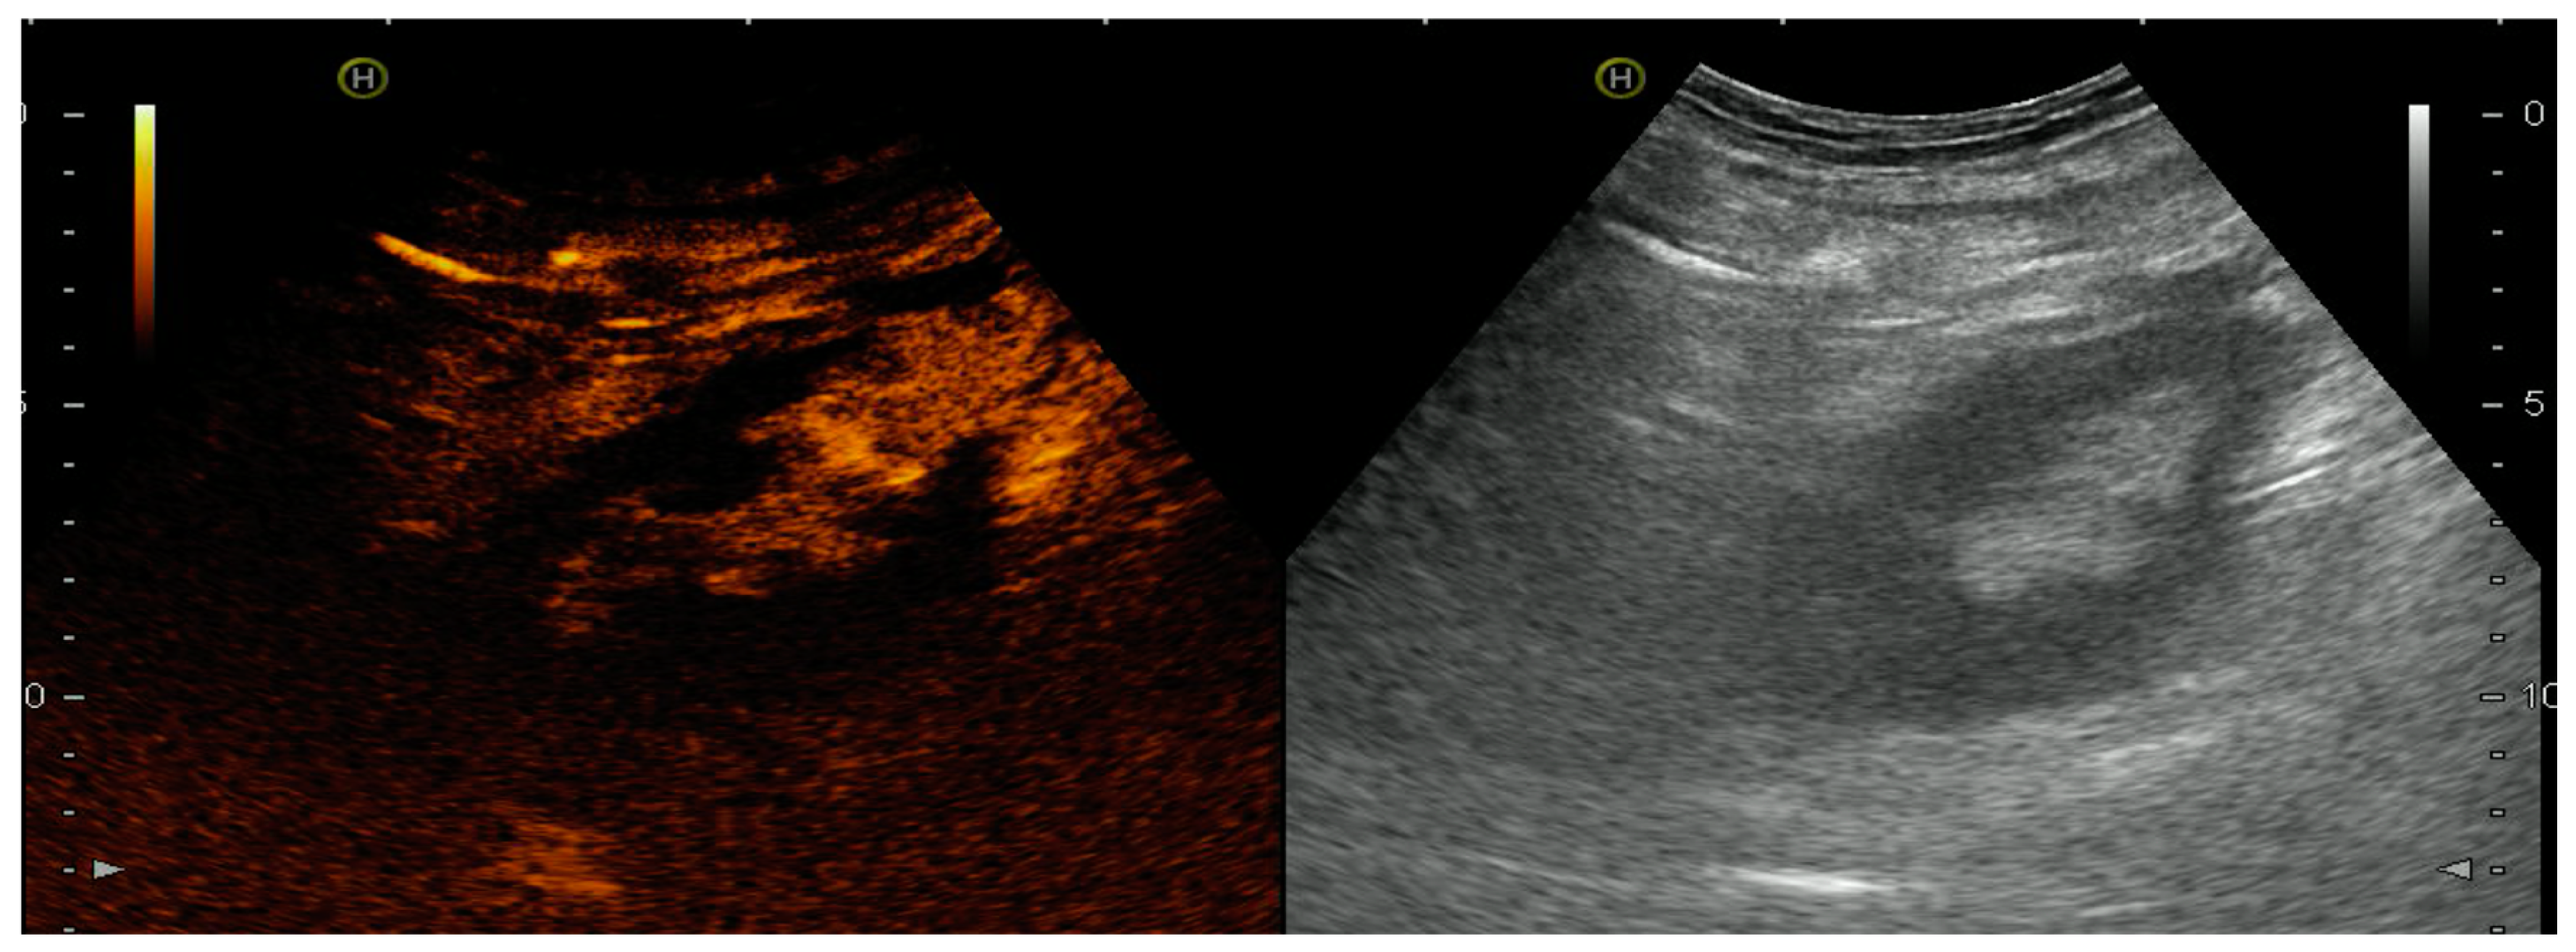

4.1.4. Infectious Complications